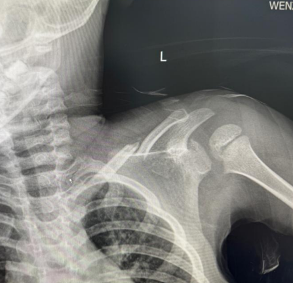

朱某,男,2016-3-15出生,因“跌倒致左肩疼痛伴活动受限2小时”2019年12月12日来我院门诊。检查发现左锁骨区见肿胀、畸形,明显压痛,左肩活动受限。本院X线摄片示:左锁骨骨折,断端明显重叠移位(图1),予以8字绷带外固定制动,定期随访。2020年1月17日复诊述左肩无肿痛,活动基本正常,摄片示:左锁骨骨折,断端对线欠佳,局部明显骨痂形成(图2)。2020年6月8日再次复查摄片示:左锁骨骨折,断端对线可,已骨性愈合(图3)。2023年9月26日再复查摄片示:左锁骨骨折部位已完成塑形,与健侧无明显差异(图4)。

图1